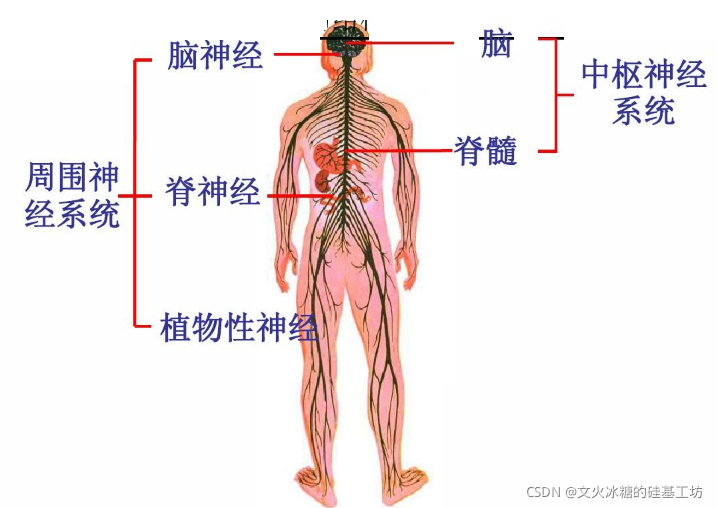

神经系统按部位可分为:

(1)中枢神经系统

- 脑,脑位于颅腔内。

- 脊髓,脊髓位于椎管内。

(2)周围神经系统(外周神经系统):

- 与脑相连的12对脑神经

- 与脊髓相连的31对脊神经。

2.2 外周神经系统的分类与组成

又称为动物神经系统, 含有躯体感觉和躯体运动神经。

主要分布于皮肤和运动系统(骨、骨连结和骨骼肌),管理皮肤的感觉和运动器的感觉及运动。

又称自主神经系统, 植物神经系统,主要分布于内脏、心血管和腺体,管理它们的感觉和运动。

含有内脏感觉(传入)神经和内脏运动(传出)神经。

内脏运动神经又根据其功能分为交感神经和副交感神经。

正式通过周围神经系统,中枢神经系统实现对人体整个器官的检测和控制。